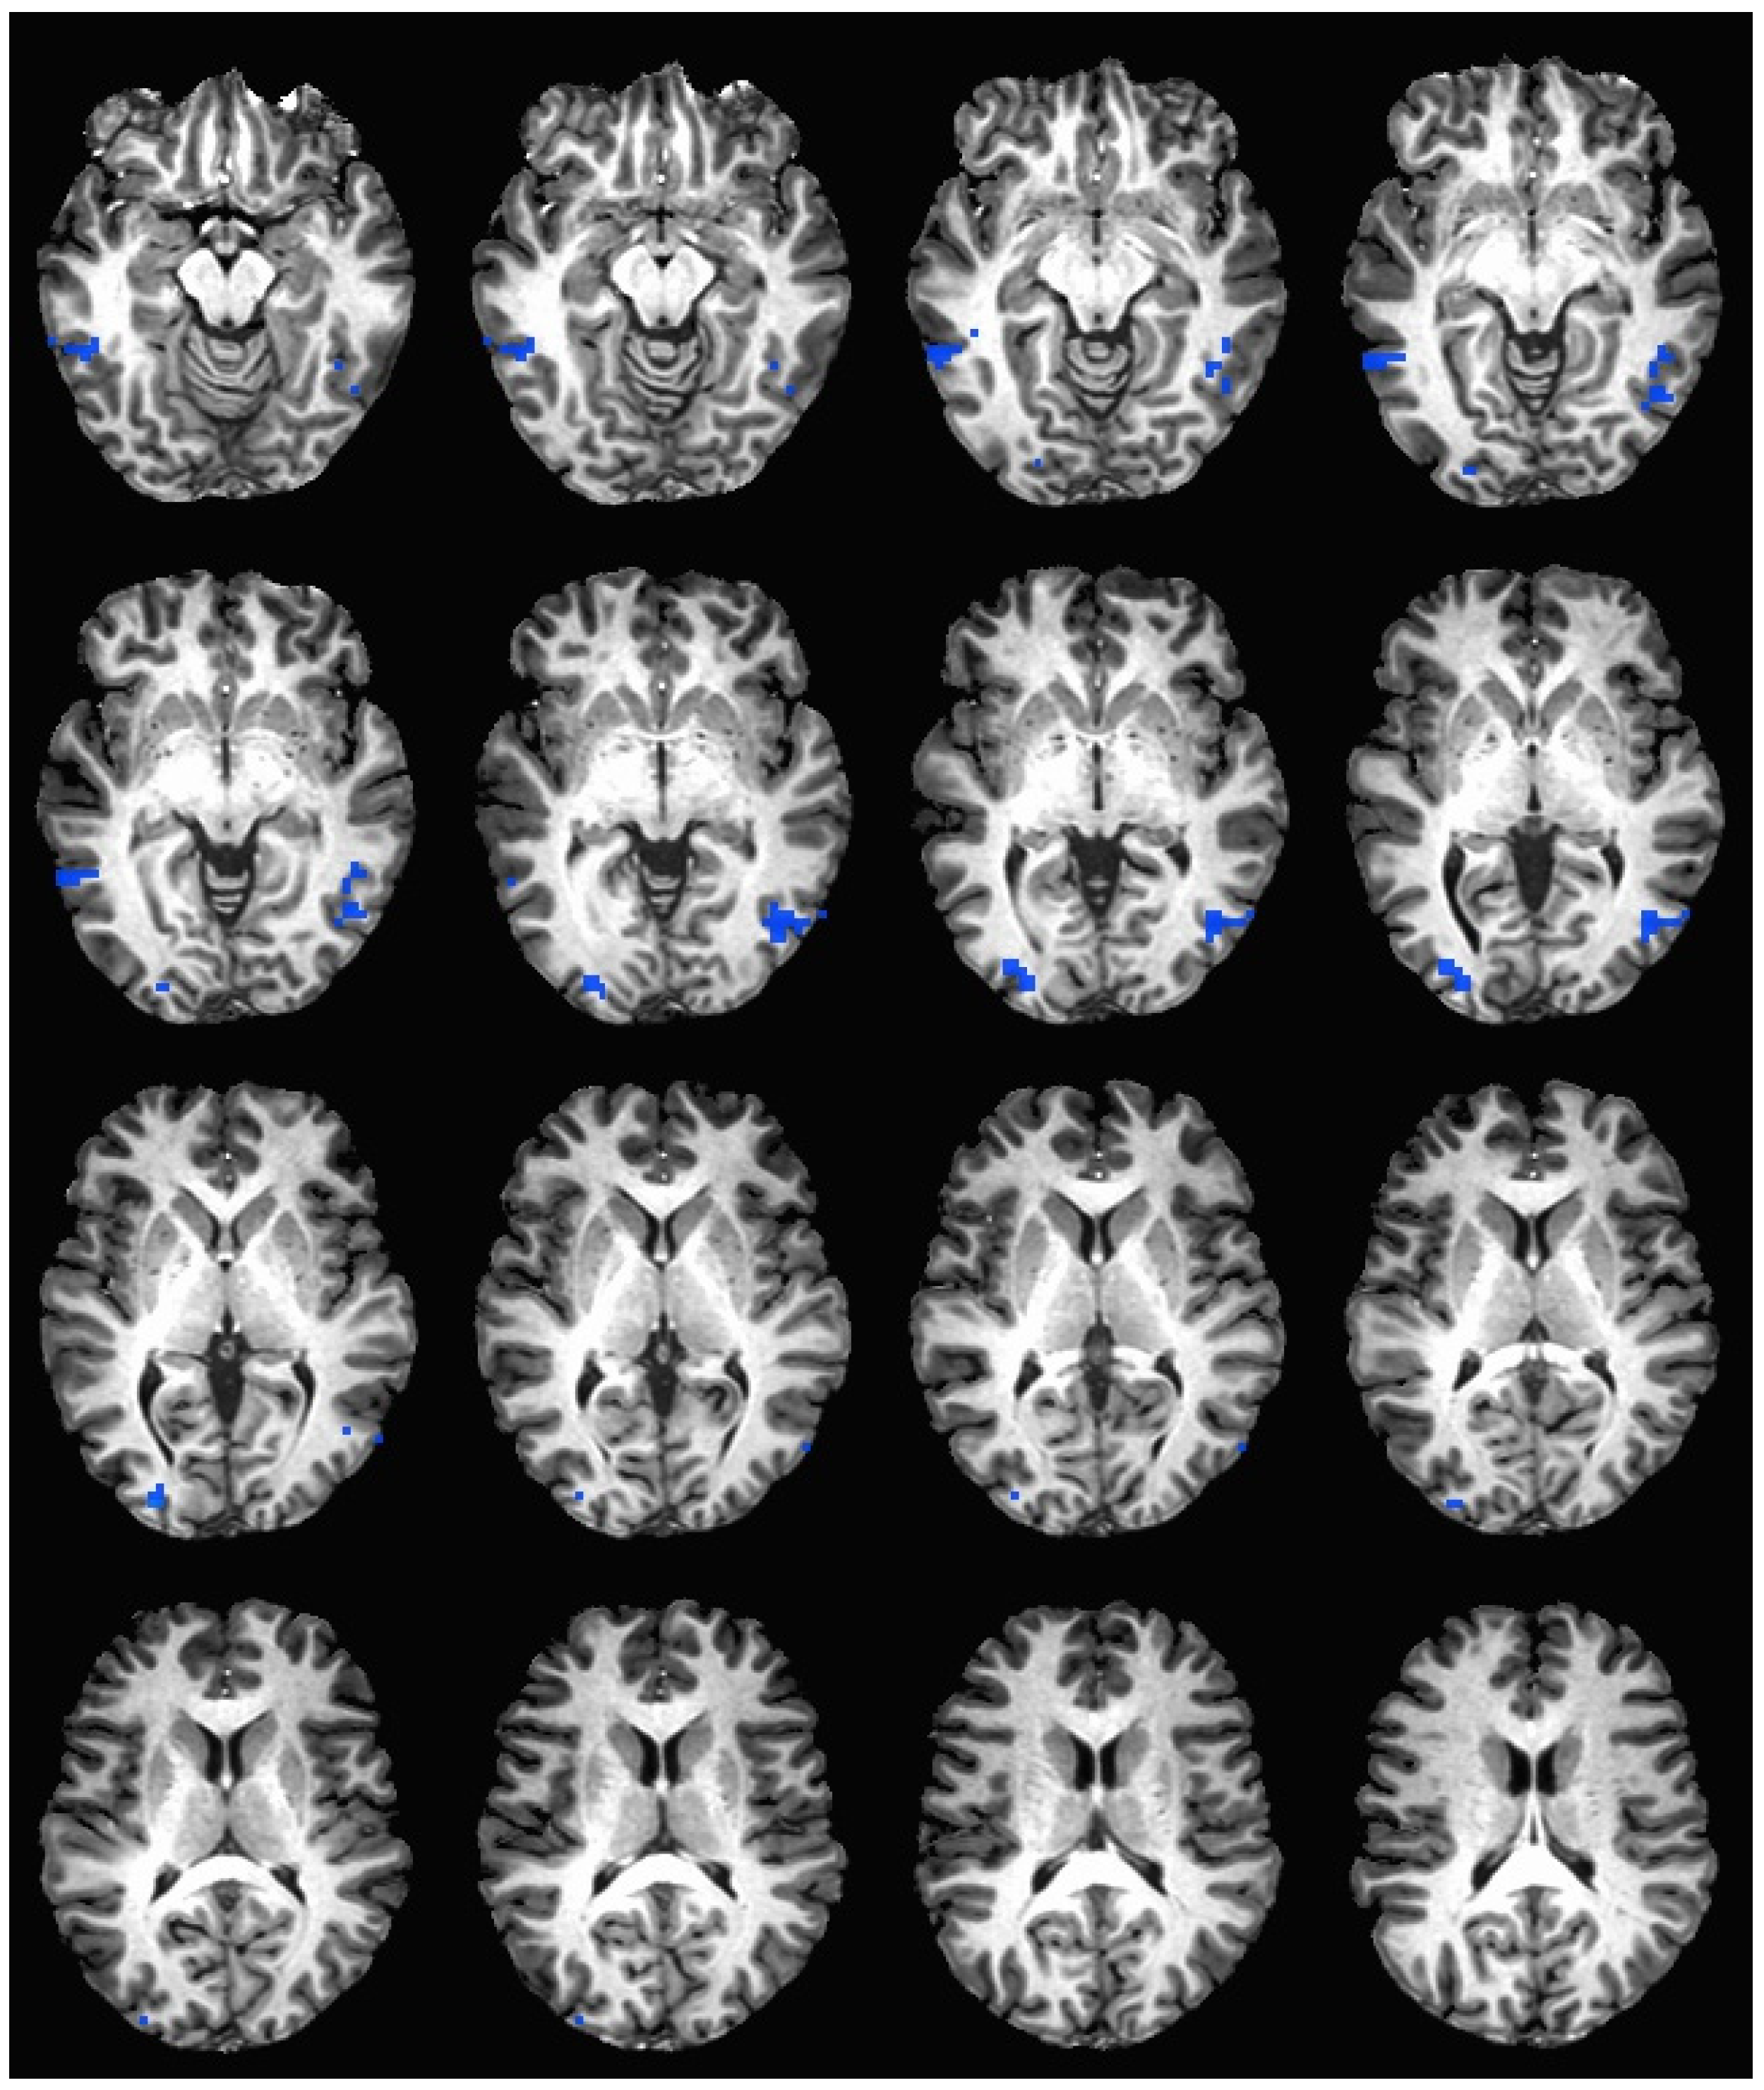

During the hedonic evaluation of saccharin, caffeine non-consumers had significantly lower neuronal activation than caffeine consumers in the middle temporal gyrus, inferior temporal gyrus, middle occipital gyrus, right fusiform gyrus, right lingual gyrus, and right cuneus (See Table 5 and Figure 3).

Figure 3. Brain activation during the hedonic evaluation of saccharin. Blue indicates areas where caffeine consumers had significantly greater activation in comparison to caffeine non-consumers.